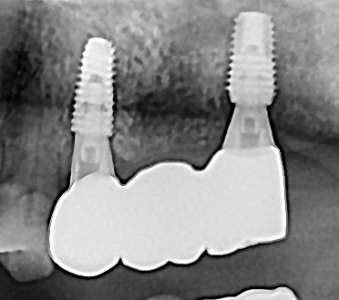

오스템 임플란트 프리미엄 BA 등급 사용

같은 오스템이라도 등급이 다릅니다. 더 빠른 골유착을 위해 프리미엄 등급을 사용합니다.

정확성 높은 치료의 시작 디지털 정밀진단 시스템

3D 디지털 데이터 기반으로 정확성 높고 정교한 치료가 가능합니다.

결과로 증명합니다.

국제모아치과의

실제 임상 증례